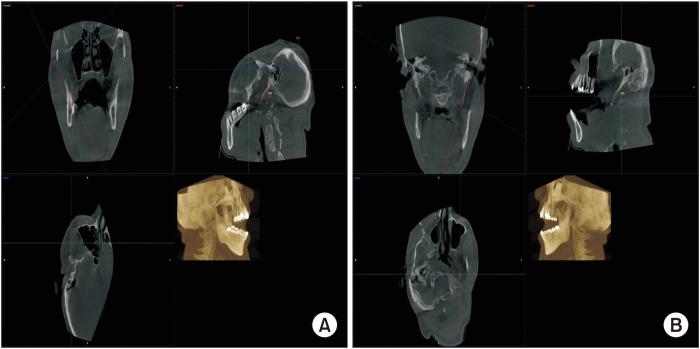

Elongated styloid syndrome (ESS) can present with myriad symptoms that mimic common features of orofacial pain, such as temporomandibular joint disorders (TMJDs), often causing a challenge and delay in diagnosis. We report the case of a 52-year-old male with a three-year history of non-painful clicking during jaw movement initially diagnosed as TMJD-related internal derangement. The patient presented with a history of annoying jaw sounds for three years, described as a popping sound without bilateral clicking or crepitation. Tinnitus and progressive hearing loss were observed in the right ear, and a hearing aid was recommended by an otolaryngologist. The patient was initially diagnosed with TMJD and managed accordingly; nevertheless, his symptoms persisted. Imaging revealed prominent bilateral styloid process elongation that exceeded the recognized cut-off level of >30 mm for elongation. The patient was informed of his diagnosis and its treatment but opted only for further swallowing and auditory assessments of his ear and nose symptoms. Clinicians should consider including ESS as a differential diagnosis in patients presenting with non-specific chronic orofacial symptoms for timely diagnosis and favorable clinical outcomes.

茎突过长综合征(ESS)可表现出无数类似口面部疼痛常见特征的症状,如颞下颌关节紊乱症(TMJD),常给诊断带来挑战并导致诊断延误。我们报告一例52岁男性病例,该患者下颌运动时无痛性弹响三年,最初被诊断为与TMJD相关的关节内紊乱。患者有三年令人烦恼的下颌弹响病史,描述为单声弹响,无双侧弹响或摩擦音。右耳出现耳鸣和进行性听力减退,耳鼻喉科医生建议佩戴助听器。患者最初被诊断为TMJD并接受相应治疗;然而,其症状持续存在。影像学检查显示双侧茎突明显延长,超过公认的延长>30 mm的临界值。已告知患者其诊断及治疗方案,但患者仅选择对其耳部和鼻部症状进行进一步的吞咽和听觉评估。临床医生在面对出现非特异性慢性口面部症状的患者时,应考虑将ESS作为鉴别诊断之一,以便及时诊断并获得良好的临床疗效。